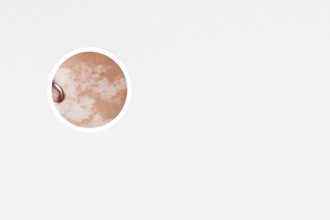

白癜風(fēng)是一種色素性皮膚病,臨床表現(xiàn)為皮膚白斑,白斑可出現(xiàn)在身體任何部位,大小不一,形狀多樣。白斑顏色呈乳白色、瓷白色、淡白色或云白色,邊緣清晰,表面光滑,無皮疹及鱗屑,白斑部位皮膚一般無顯然感覺異常,但部分患者可能會(huì)有輕微的瘙癢或灼熱感。白癜風(fēng)不是癌癥,不會(huì)危及生命,但會(huì)影響患者的外觀,導(dǎo)致心理負(fù)擔(dān),甚至影響患者的社交活動(dòng)。